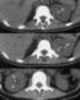

Renal calculi in hydronephrosis

Hydronephrosis describes hydrostatic dilation of the renal pelvis and calyces as a result of obstruction to urine flow downstream. Alternatively, hydroureter describes the dilation of the ureter, and hydronephroureter describes the dilation of the entire upper urinary tract (both the renal pelvicalyceal system and the ureter). [Source: Wikipedia ]